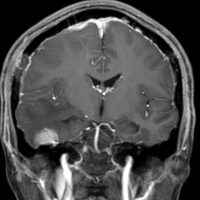

全髄膜の腫瘍化,NF-2

テント下を含めて頭蓋内の全ての髄膜が同時に腫瘍化してきます。この患者さんはNF-2なのですが,NF-2がない患者さんにもmeningiomatosisはあります。脳圧亢進による視神経乳頭萎縮で両側の視力が無くなるというような症状が出ます。これは手術適応がないタイプです。